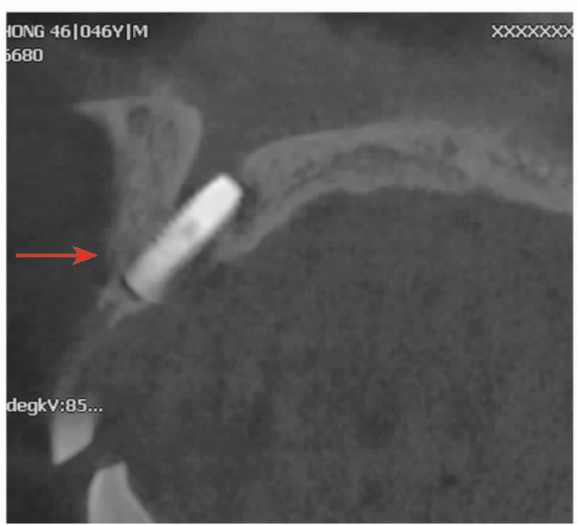

下牙槽神经管是下颌骨非常重要的结构,当下牙槽神经管损伤后会出现麻木或者其他的症状。误读全景片或者不了解全景片的失真率往往是造成手术意外的原因(图7)。

图7 全景片及CBCT冠状位A.全景片显示种植体压迫下牙槽神经管上壁;B.CBCT冠状位显示种植体进入下牙槽神经管内

对于全景片上神经管影像不清晰或者不能确定时,最好用CBCT检查,以确定神经管的位置,有没有其他分支,距离牙槽嵴的高度,颊舌侧的宽度以及有无颏孔舌侧开口等。在下颌骨骨量不足的情况下,种植手术时要高度警惕,尽量避免种植体进入下牙槽神经管(图8)。